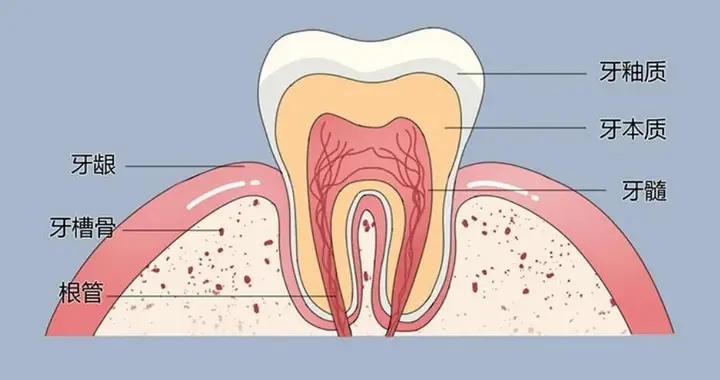

此牙痛非彼牙痛,牙痛也是有不同种类之分的!